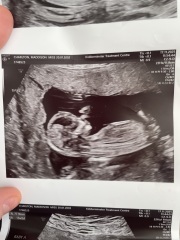

Maddie020200 · 17/11/2025 13:48

Please help boys or girls

both twins are indentical

Nub theory ?